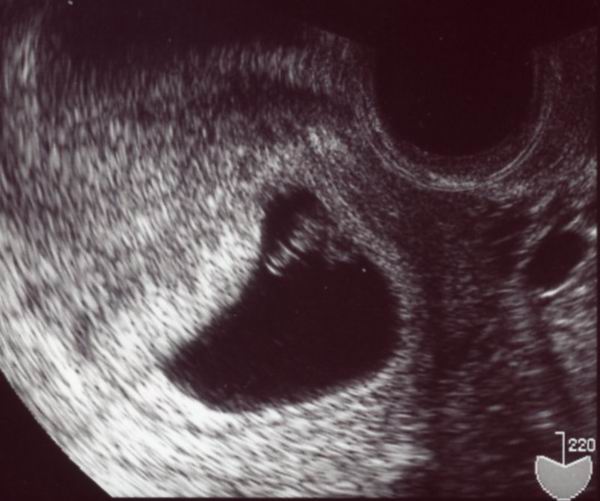

さて,気になるエコーは…。

前回「赤ちゃんではない」と言われた輪っかっぽいものの近くに

白く別の丸っこいものが写っています。

「ああ,見えましたね~。これが赤ちゃんですよ

」

言われた瞬間,なんだか涙が出そうなくらいに感動。

ちゃんと育ってるんだなー!

私には分からなかったんだけど,

「赤ちゃん動いてますよ。大丈夫,元気だ」

と言われました。